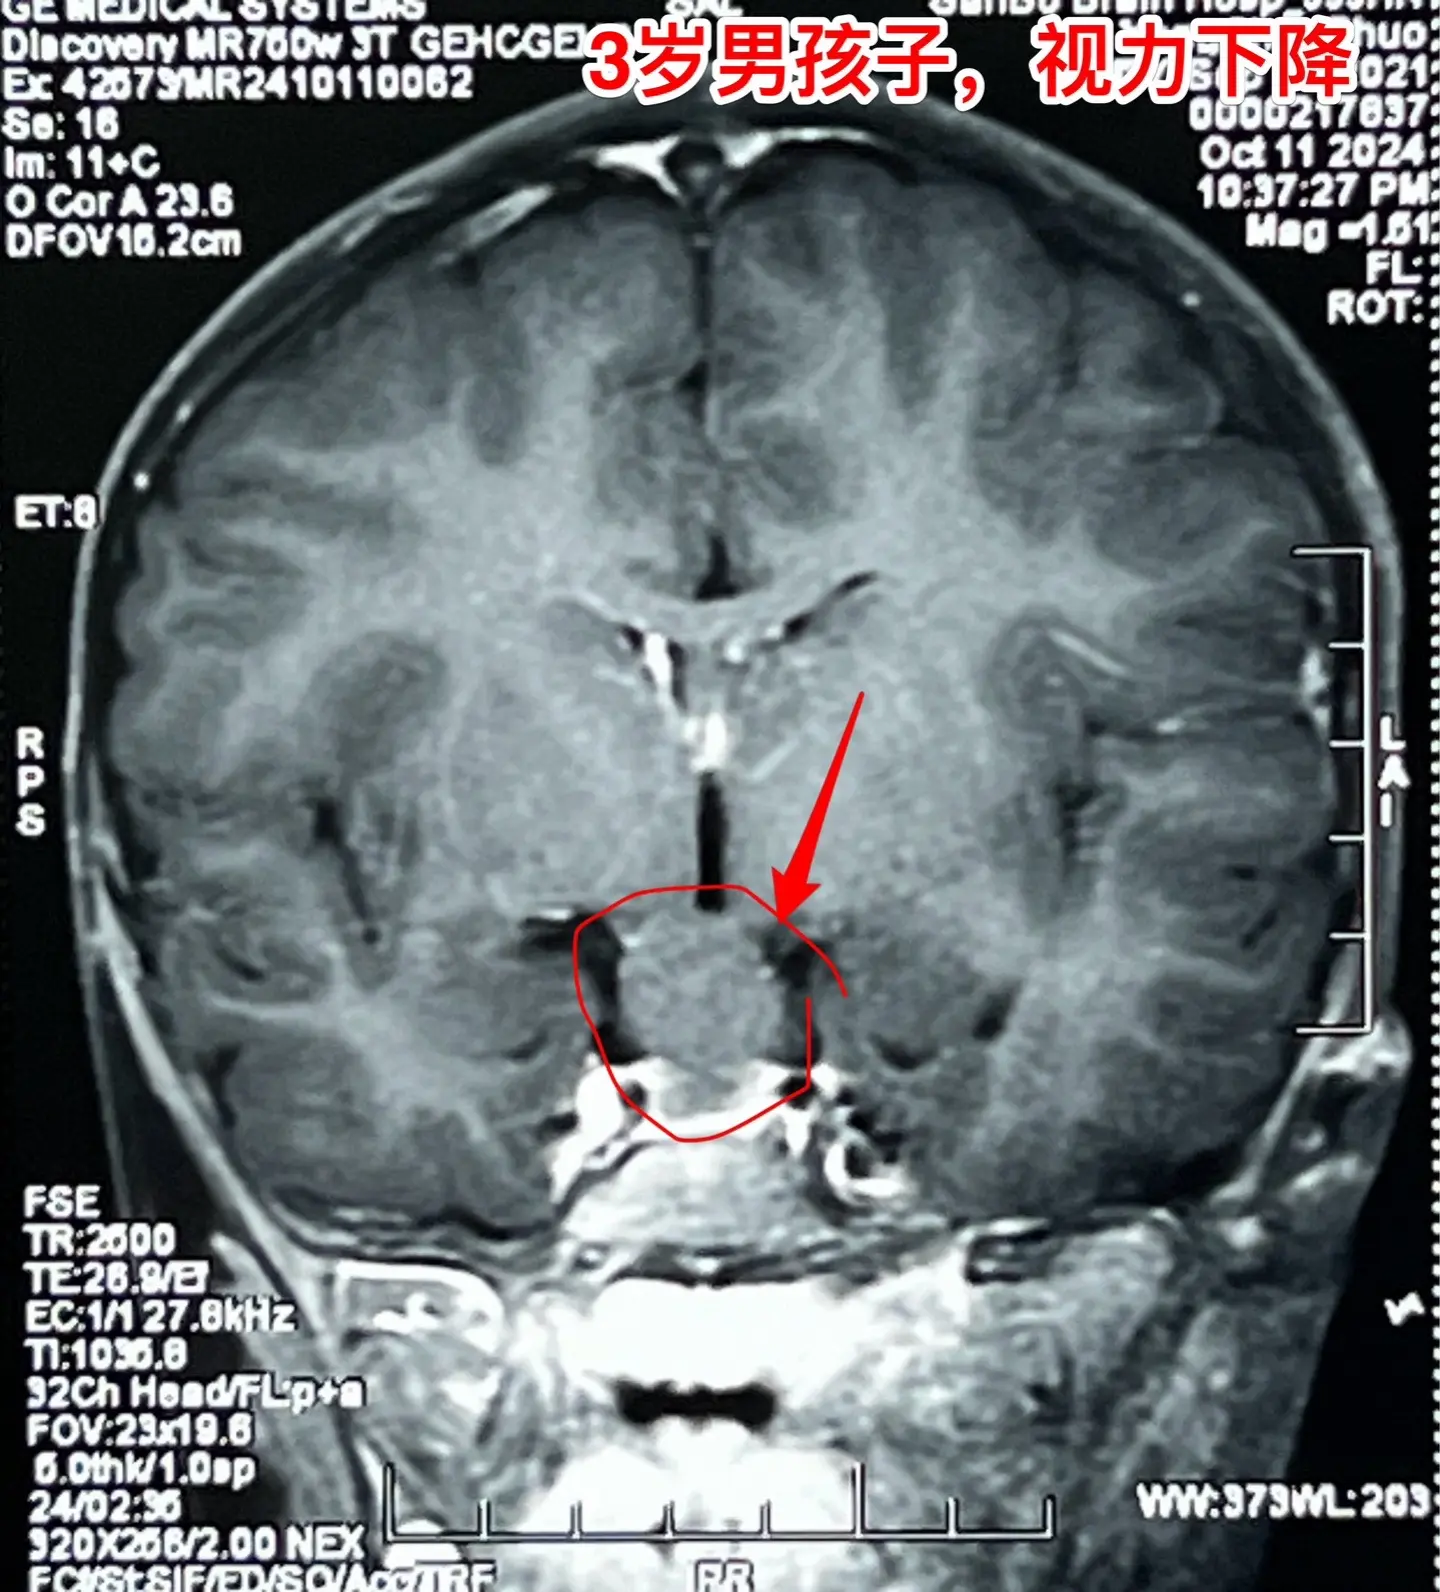

鞍区高密度囊肿-高密度不等于钙化。拉克氏囊肿在CT扫描中大多数呈低密度影,少数呈现比较均匀的高密度影,但是绝对不是钙化。不能误认为是颅咽管瘤。 三岁男孩子因偶然原因行CT扫描发现鞍区病变。测视力才发现患儿的视力有下降(0.3)。根据CT、磁共振可以判断这是拉克氏囊肿,病变没有钙化。 拉克氏囊肿如果压迫视神经、视交叉造成视力下降或者视野缺损,则有手术指征。 今日10.25经翼点入路将病变切除。术中快速冰冻报告为拉克氏囊肿。